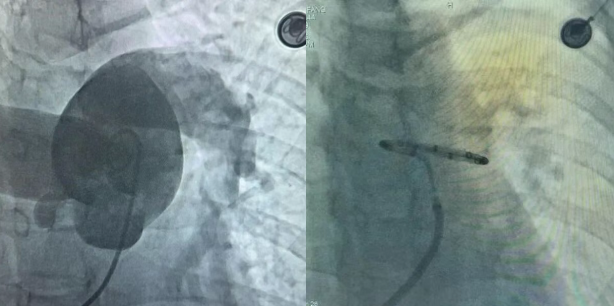

手术过程中,钟炜主任医师与团队其他成员紧密配合,通过右心导管检查、DSA肺动脉造影,并结合术前肺动脉CTA解剖结构特征,选择最佳型号的PADN消融导管,送至患者的肺动脉治疗靶点位置,精准定位后释放射频能量,有效地去除了目标位置的交感神经活性。整个手术过程顺利,术中各监测指标平稳。 随后,撤出消融导管,待患者心率恢复至术前水平,再次行RHC右心导管检测,撤出导管及鞘管,确认无血管穿孔、血栓形成。

此次手术术后即刻观察到患者肺动脉压力下降8.9%,肺血管阻力下降16.5%,心输出量上升22.7%,患者中远期肺动脉压力、肺血管阻力及心输出量将进一步改善,手术圆满完成。术后患者恢复良好,血氧饱和度由术前85%-90%之间,上升至92%-98%,趋于正常水平,以前患者上半层楼就会气急,需要大口深呼吸,现在活动能力明显改善,胸口无不适,出院前6分钟步行试验距离达360m,手术效果满意。